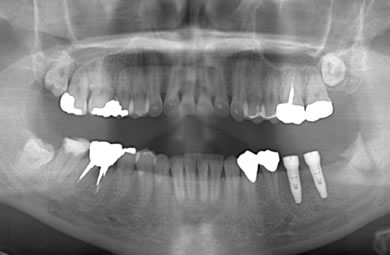

インプラントの症例写真 IMPLANT

インプラント治療+セラミック治療

| 治療方針 | 臼歯部の審美的・機能的回復をインプラント治療とセラミック治療にて行う。 | ||||||||||||||||||||||||||||||||

| 治療内容 | インプラント1本、メタルボンドセラミック2本 | ||||||||||||||||||||||||||||||||

| 総治療費 | 572,750円 | ||||||||||||||||||||||||||||||||

| 治療期間 | 3ヶ月 |